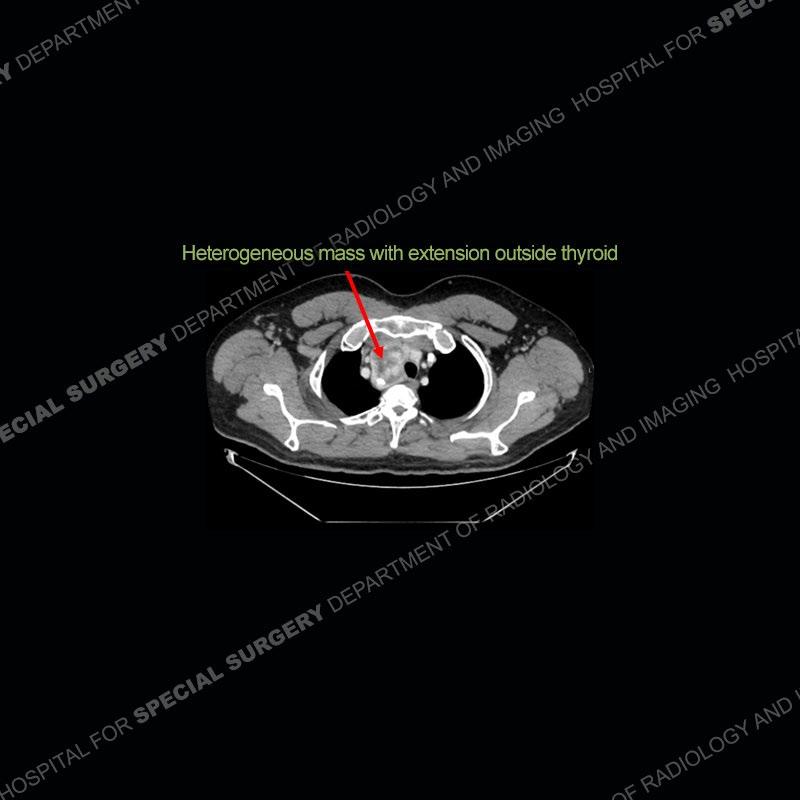

Findings

The chest radiographs demonstrate a leftward deviation of the trachea. CT images demonstrate a large, somewhat heterogeneous mass of the thyroid that extends outside the confines of the thyroid tissue. There is a subtle, enhancing soft tissue mass of the proximal right humerus. Slightly prominent mediastinal lymph nodes are present with additionally, multiple supraclavicular lymph nodes.

Over the years we have shown a couple of these cases which may be considered more so an “eye test” then anything else. In clinical practice, these are often very difficult cases as the initial finding of the tracheal deviation may be easily overlooked. Screening radiographs are clearly most often used to assess cardiopulmonary function before induction of anesthesia but at times other findings of great and unfortunately grave consequence can be found. The evaluation of the incidental thyroid mass on CT and MRI is an ever changing situation. Parameters such as age of patient, extension outside of the thyroid, enhancing nodules, and local invasion of lymph nodes are evaluated to see if a lesion needs to be further evaluated.

Although not strictly a part of the evaluation of an “incidental” thyroid lesion, evaluation of the adjacent lymph nodes and bony structures can also be quite important. In this case, there is an enhancing mass of the right humerus. This is very subtle and can only really be recognized by evaluating the density of the bone. Typicaly marrow will have a fatty density or nearly fluid density. As the density, as in this case, approaches soft tissue an infiltrative process must be entertained. Thyroid mets are markedly vascular accounting for the areas of enhancement of the humeral mass. The mediastinal and supraclavicular lymph nodes although not individually enlarged, should raise suspicion of an underlying inflammatory/neoplastic process.